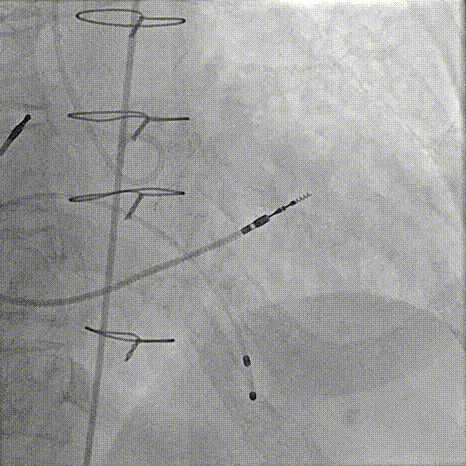

器械过弓柔顺